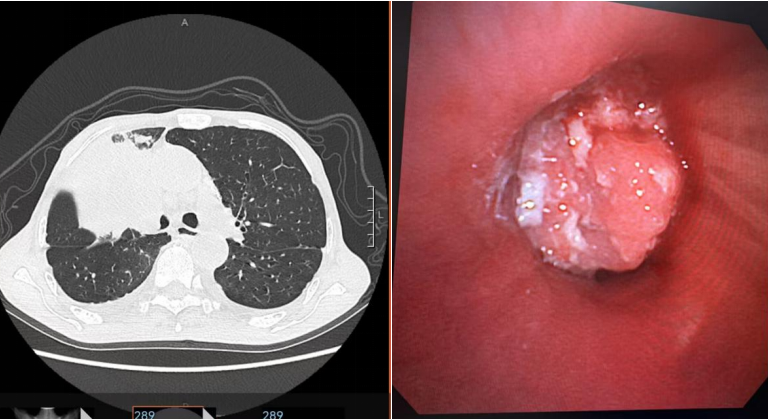

患者王先生(化名),79岁,因“咳嗽、咳痰及气促2月”入院。影像学检查显示右肺上叶支气管占位,右肺上叶阻塞,右肺通气功能严重受阻,活动后明显气促。气管镜下见右主支气管远端被肿瘤几乎完全阻塞,短期全身静脉化疗不能及时解除患者呼吸困难症状,经科室讨论后,建议先行支气管镜下肿瘤切除术开通患者气道,再行静脉化疗。

1.精准定位:在全麻下,张冀松博士、安宇主任领衔团队将支气管镜经气管插管送入气道,高清镜头实时锁定肿瘤部位(右主支气管);